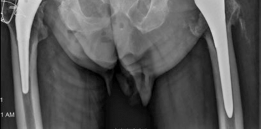

For anyone wondering about Acetabular Revision: Solving Challenges Post Two-Stage Arthroplasty, A **title acetabular revision** is a complex procedure addressing issues like septic loosening, dislocation, and significant osteolysis in total hip arthroplasty. For a 71-year-old male with a dislocated left THA due to infection and periacetabular bone loss, treatment involved a two-stage exchange followed by revision with a press-fit hemispherical cup and screw fixation.

Standard anteroposterior pelvis and cross-table lateral radiographs are mandatory. Judet views (iliac and obturator obliques) are critical for assessing the integrity of the anterior and posterior columns. However, plain radiography often underestimates the extent of osteolysis and bone loss.